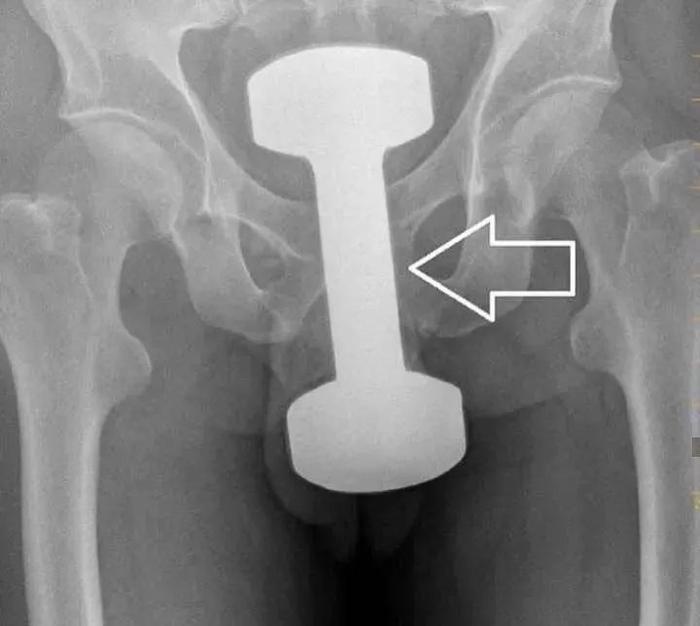

有塞杠铃的,这哥们拿这玩意练完自己的肱二头肌,又想去练括约肌,也是挺让花姐出乎意料的。